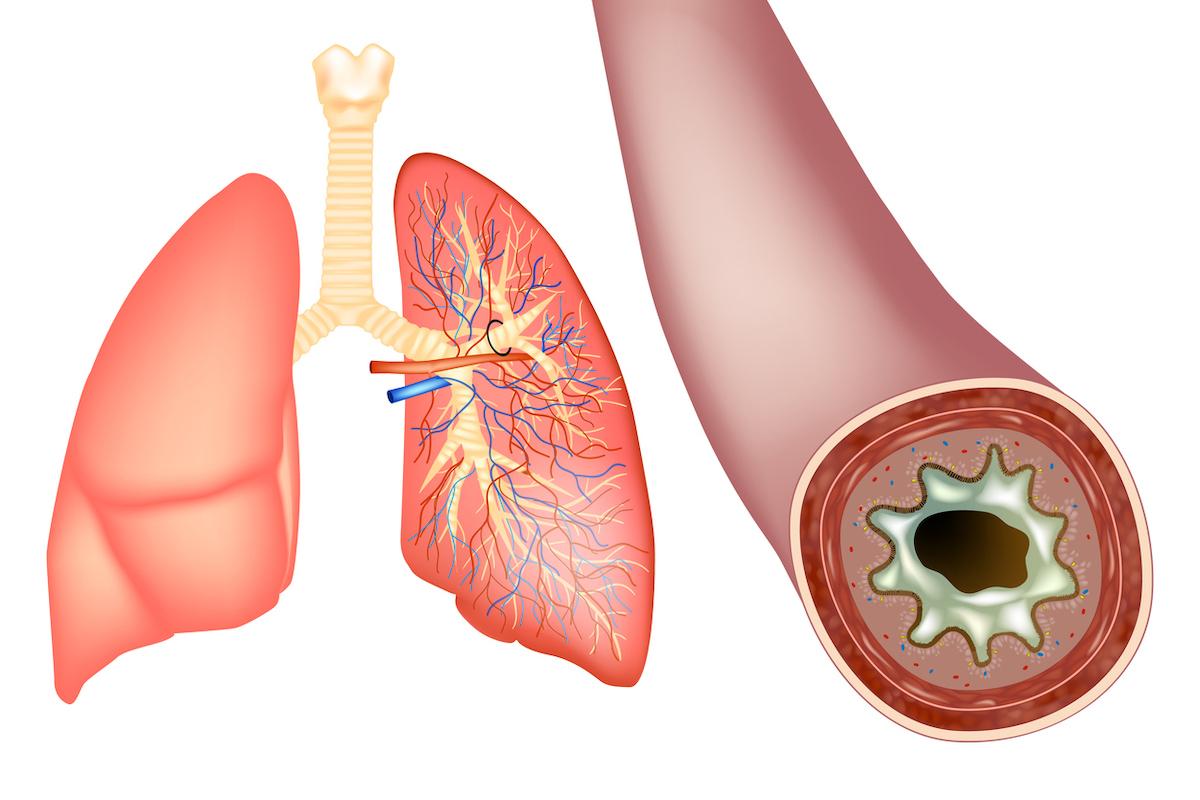

- utah778/ISTOCK

Le cancer du poumon est la première cause de décès par cancer dans le monde, selon l’Organisation mondiale de la santé. Pour le soigner, plusieurs traitements sont utilisés, dont la chimiothérapie, la radiothérapie et l’immunothérapie. Des scientifiques travaillent sur de nouvelles techniques pour améliorer leur efficacité et permettre aux patients de gagner en espérance de vie. Dans le dernier numéro de la revue Nature, paru le 6 décembre, des chercheurs américains présentent l’une de ces nouvelles voies de traitement : l’utilisation combinée d’un médicament anti-allergique avec l’immunothérapie pour booster le système immunitaire face aux tumeurs.